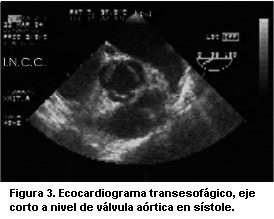

CASO 1

Figura 3. Ecocardiograma transesofágico, eje corto a nivel de válvula aórtica en sístole.

A estos dos pacientes internados por accidentes isquémicos transitorios se les encontraron masas en la válvula aórtica con características ecocardiográficas similares: eran pequeñas, pediculadas, múltiples, con temblor sistólico y sin disfunción valvular. Ninguno de ellos tenía historia previa o reciente de fiebre u otros elementos sugestivos de infección. En este contexto, y considerando las características ecocardiográficas, se hizo diagnóstico presuntivo de fibroelastoma papilar aórtico, y ambos pacientes fueron derivados a cirugía cardíaca.

A pesar de que las características ecocardiográficas eran similares, el examen anatomopatológico reveló que las masas correspondían a vegetaciones cicatrizales en el primer caso y a fibroelastoma papilar aórtico múltiple en el segundo.